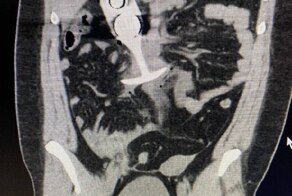

Оказалось, что в Америке стоимость МРТ составляет около 5000 долларов, что эквивалентно примерно 400 тысячам рублей. А тут они заплатят 40 долларов, что составляет примерно 4 тысячи рублей.

Программа предлагает МРТ от $250 в зависимости от области тела и клиники. В стоимость входит всё: сама процедура, расшифровка результатов и копия снимков. Доступно во многих городах США. (radiologyassist.com)

Фиксированная цена $499 за МРТ без направления от врача. Включает полный медицинский отчёт и снимки. Центры находятся в штатах Джорджия и Алабама. (expressmri.com)

Предлагает полное МРТ-сканирование тела по цене от $1,350 до $2,500, ориентированное на раннее выявление заболеваний. (newyorker.com)